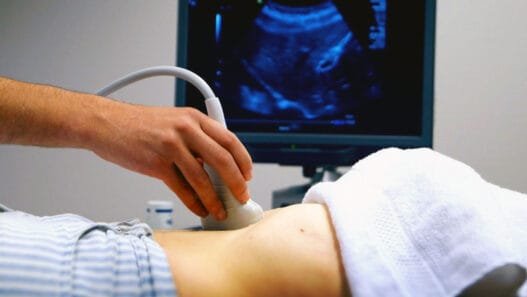

Ayrıntılı Ultrason Nedir ve Nasıl Uygulanır?

“Ayrıntılı ultrason” ya da diğer adıyla “detaylı ultrasonografi”, anne karnında büyüyen bebeğin organlarının oluşumunu ve gelişimini inceleyen bir görüntüleme yöntemidir. Bu yöntem, özellikle bebeğin beyin, kalp, akciğer, böbrek gibi önemli organlarının gelişimini takip etmeyi amaçlar. Ayrıntılı ultrasonografi ile bu organların büyüme sürecinde bir sorun olup olmadığı belirlenebilir. Bebeğin beyni, gözleri, burnu, dudakları, kalbi, kolları, bacakları gibi birçok bölgesi ayrıntılı olarak değerlendirilir ve doğum öncesi olası yapısal anomali riskleri incelenir.

Anne karnındaki bebeğin gelişimi iki ana döneme ayrılır: embriyolojik dönem ve fetal dönem. İlk 8 hafta embriyolojik dönem olarak adlandırılır ve bu süreçte bebeğin temel yapıları oluşmaya başlar. Bu dönemden sonra gelen fetal dönem ise 8. haftadan doğuma kadar devam eder ve bu süreçte bebeğin tüm organları hızla gelişmeye devam eder. Ayrıntılı ultrasonografi genellikle fetal dönemin 18-24. haftaları arasında uygulanır. Bu dönemde bebeğin organları büyük ölçüde oluşmuş olduğundan, detaylı bir inceleme yapmak mümkündür. Ancak, gelişen teknoloji sayesinde bu inceleme artık 11-13. haftalar arasında da yapılabilmekte ve böylece erken teşhis şansı artmaktadır. Yine de bazı yapısal bozukluklar bu haftalarda görülemeyebilir, bu nedenle özellikle beyin ve kalp ile ilgili detaylı değerlendirmeler için 20-24. haftalarda tekrar ultrason önerilir.

Ayrıntılı ultrasonografi, kullanılan yüksek frekanslı ses dalgalarıyla bebeğin detaylı görüntülerini elde eder. Bu işlem, tamamen güvenlidir ve hem anneye hem de bebeğe herhangi bir zarar vermez. Ultrason süresinin uzun olması nedeniyle bazı anne adayları bebeklerinin bu işlemden olumsuz etkilenebileceği kaygısını taşıyabilirler. Ancak bilimsel çalışmalar, bu cihazların bebeğe hiçbir zararı olmadığını ve güvenle kullanılabileceğini göstermiştir. Ultrason sırasında kullanılan ses dalgaları, vücutta radyasyon gibi zararlı etkiler yaratmaz; dolayısıyla bu işlem tamamen güvenlidir.